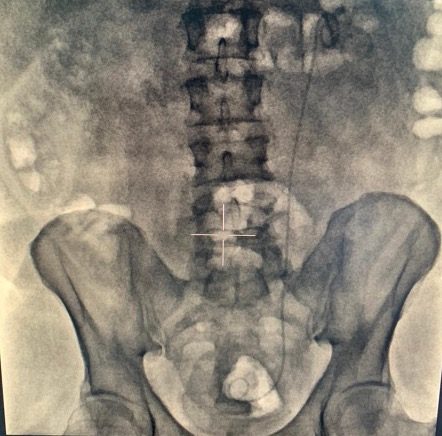

Обзорная урограмма до операции (рис. 1).

Краткая информация о пациенте Пациент Г., 45 лет. Считает себя больным в течение года, когда впервые был госпитализирован в городскую районную больницу с левосторонней почечной коликой. На момент обращения выявлен камень левого мочеточника, по поводу чего (10.08.2020 г.) выполнялась контактная уретеролитотрипсия слева, установка внутреннего мочеточникового стента. В последующем для удаления стента в стационар не обращался. С июня 2021 г., стал отмечать боль в поясничной области слева. Обследовался амбулаторно, по результатам компьютерной томографии диагностированы внутренний мочеточниковый стент слева, камень в мочевом пузыре на дистальном конце стента, размерами до 3,8 см и коралловидный камень в левой почке, размерами до 3,4 см. Госпитализирован в клинику урологии для оперативного лечения.